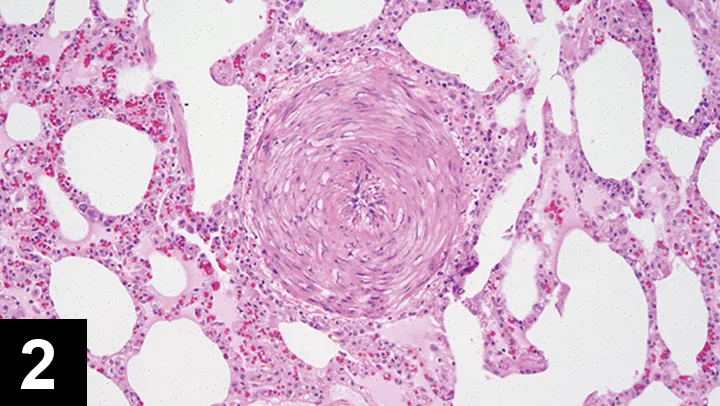

• Heartworm infection can be arrested at this stage, but histologic changes (Figure 2) and clinical signs may persist.

Figure 2. Histopathology of the pulmonary artery of a cat infected with D immitis. Courtesy of Dr. Julia A. Conway